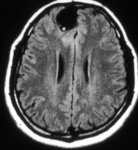

Granular stage - neurocysticercosis: MRI scan showing enhancing lesion without perilesional oedema

From the personal collections of Dr Christina Coyle and Dr Maheen Saeed; used with permission